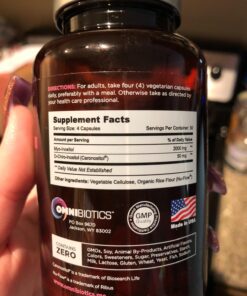

Myo-Inositol Plus & D-Chiro-Inositol | PCOS Supplement | Helps Promote Hormone Balance and Support Ovarian Function | Natural Fertility Supplements (120 Capsules)

Description

Myo-Inositol is the most abundant form of inositol which is an important

nutrient to help support the female reproductive system. D-Chiro-Inositol has

been studied for its ability to improve absorption and bioavailability.

OmniBiotics Myo-Inositol Plus with Caronositol features myo-inositol and

d-chiro-inositol at 2,000 mg and 50 mg each respectively, per serving. Myo-

Inositol Plus is a safe and effective myo inositol with d chiro supplement

option. 120 veggie caps 30 day supply These statements have not been

evaluated by the FDA. This product is not intended to diagnose, treat, cure,

or prevent any disease. Caronositol is natural D-chiro-inositol botanical

extract (minimum 95%) purified from carob pod by a solvent-free patented

process. ‣ Made In the USA within a FDA inspected, NSF and cGMP certified

facility ‣ 100% vegetarian / vegan friendly, Non-GMO ‣ Contains no gluten,

wheat, dairy soy, yeast, animal products, artificial colors, or artificial

preservatives

Features:

- HORMONE + FERTILITY + MENSTRUAL CYCLE SUPPORT Specially formulated for women, Myo-inositol Plus contains ingredients that are clinically proven to naturally help support hormone balance, help maintain ovarian function, promote healthy menstrual cycles, and support egg quality. Myo-Inositol Plus is a 100% natural fertility supplement, designed to promote overall reproductive health.

- MOST EFFECTIVE 40:1 RATIO Studies show that the bodys natural 40:1 ratio of Myo-Inositol to D-Chiro-Inositol is the most effective ratio for fertility and reproductive support. Myo-Inositol Plus offers this clinically-proven 40:1 ratio and features Caronositol, a natural D-chiro-inositol (DCI) botanical extract (minimum 95%), purified from carob pods through a solvent-free patented process.

- PROMOTES EMOTIONAL WELLNESS + MOOD Myo-Inositol is widely used to help support energy and promote an overall feeling of well-being because the brains natural neurotransmitters (dopamine, norepinephrine, serotonin, acetylcholine, and GABA) rely on inositol to relay messages. Myo-Inositol Plus was designed to maximize these positive emotional effects.

- SUPPORTS WELL-BEING Myo-Inositol is included in our formula for its contribution to overall women's health, with a focus on promoting balance and well-being in the body. It is designed to complement a healthy lifestyle, supporting the body's natural processes.

- 100% NATURAL, NON-GMO, NO BINDERS or ADDITIVES Our clinical-strength, Myo-Inositol Plus supplement is 100% free of: gluten, soy, nuts, dairy, sugar, animal by-products, artificial ingredients, chemicals, preservatives and fillers. We also do testing at every stage of the manufacturing process to ensure all ingredients are free of heavy metals. Made in the USA in a NSF-certified, FDA-registered, cGMP facility.

Product Details:

- Brand: OmniBiotics

- Flavor: Unflavored

- Primary Supplement Type: Myo-Inositol

- Unit Count: 120.00 Count

- Item Form: Capsule

- Item Weight: 0.14 Kilograms

- Item Dimensions LxWxH: 4 x 4 x 5 inches

- Special Ingredients: Vegetarian, Gluten Free, Vegan

- Diet Type: Vegetarian, Gluten Free, Vegan

- Product Benefits: Hormone Balance

- Is Discontinued By Manufacturer : No

- Product Dimensions : 4 x 4 x 5 inches; 4.8 Ounces

- Date First Available : October 14, 2016

- Manufacturer : OmniBiotics